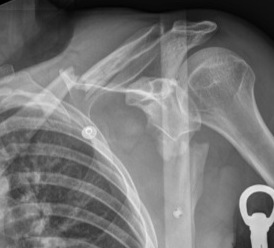

Scapula blade fractures

Indications for surgery

| Glenoid neck displacement | Glenoid neck angulation | Glenopolar angle |

|---|---|---|

| > 2cm medial displacement | > 45° angular deformity | < 22° glenopolar angle |

Other

- floating shoulder

- combined scapular fracture / intra-articular glenoid fracture

Medial displacement

Angulation

Glenopolar angle